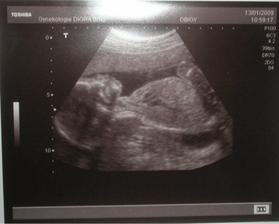

4. led 2009

Ani jsme se moc nesnažili a ono to vyšlo 🙂 pozitivní těhotenský test jsem si dala jako dárek ke svým narozeninám 22.9.2008. A jako další dáreček bylo 2 dny před Vánocemi, že to bude kluk!! Holčičku jsem sice obrečela :( , ale už jsme si zvykli. Těšíme se na našeho Samuelka!!!!